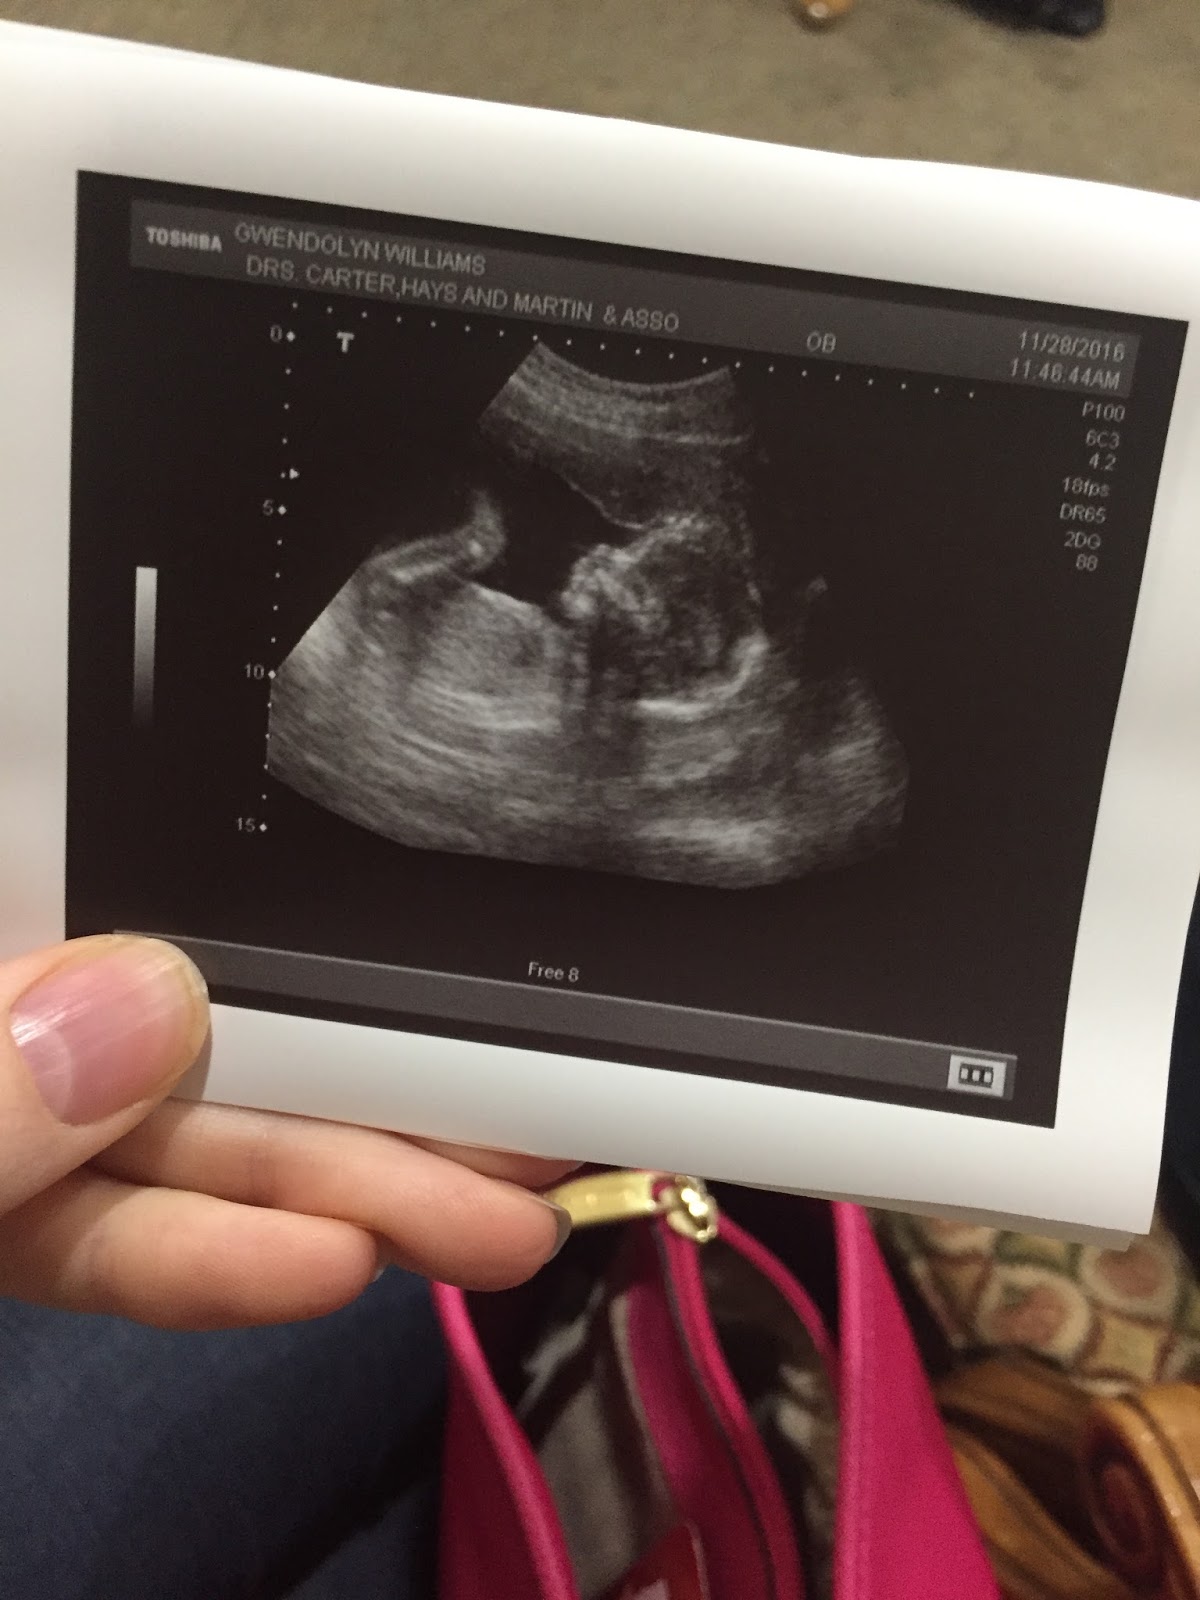

We had our midway point anatomy scan last week - that's the "big" sonogram where they take a bunch of measurements of the baby (bones, organs, etc.) to make sure everything is on track. Baby boy is doing great! He's measuring about a half a week smaller than expected, but that's normal - plus Arden was always a little bit on the small side. Honestly, it wouldn't surprise me if my due date was off (ahead) by a week or two. It's all just guesswork anyway. We'll see!

It's always so much fun getting to see glimpses of the baby during sonograms! We got to see him moving his legs and even sticking his tongue out. It's amazing to be able to watch his little heart beat. The sonographer did confirm that baby W#2 is a boy, but we already knew that!

The only moderately concerning thing that happened during our visit is that apparently my placenta has a lake. Sounds funny, doesn't it? It's nothing to be too concerned about, and apparently fairly common, but basically there is a pool of blood near my placenta. My doctor just wants to keep an eye on it so it means we'll get to have another sono next time - I'll take it! I don't think we would have had another one until the very end, so while I don't want there to have to be a reason to check in again on our little guy, I'm kind of excited that we'll get to see him again right after Christmas.